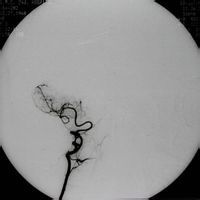

基本信息 配伍的女性經長時間站立後出現孤立性踇趾不能背伸,可能與長時間的踝關節趾屈,腓總神經以腓骨頸為支點受到牽拉損傷從而導致踇長伸肌受累有關。(三)檢查...及其治療過程中較常發生。表現為小腿前外側伸肌群麻痹,出現輕微的肌無力甚至...

一、腓總神經: 二、腓總神經損傷: